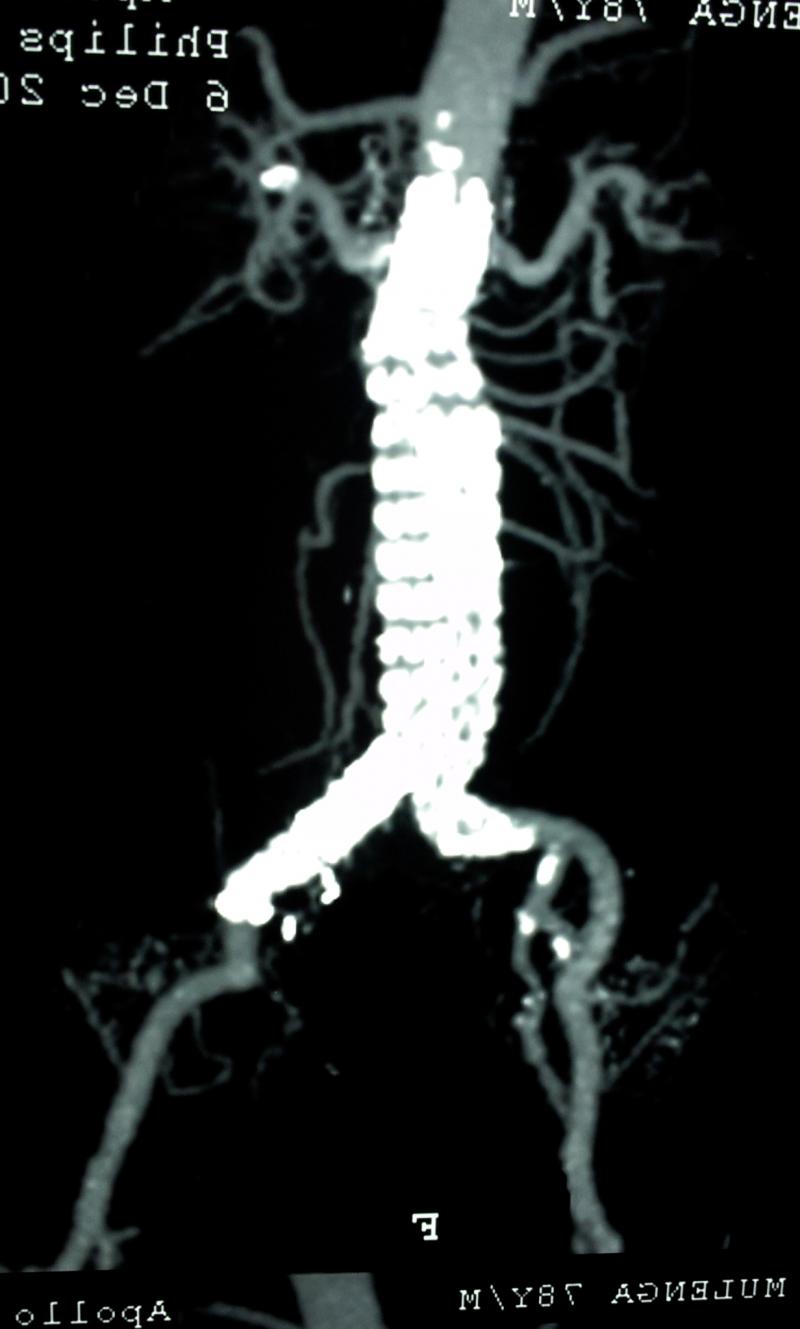

Recently, (October 2016) we have been able to perform total aortic debranching of the thoraco-abdominal aorta and then perform an EVAR . In this case, the complete branches to the abdominal organs were bypassed from bilateral iliac arteries. The arteries bypassed were the Coeliac, superior mesenteric, left hepatic, abberant right hepatic artery and both renal arteries. This is termed as Aortic debranching operation.The patient is doing well

The above is the aneurysm and below is the scan after repair